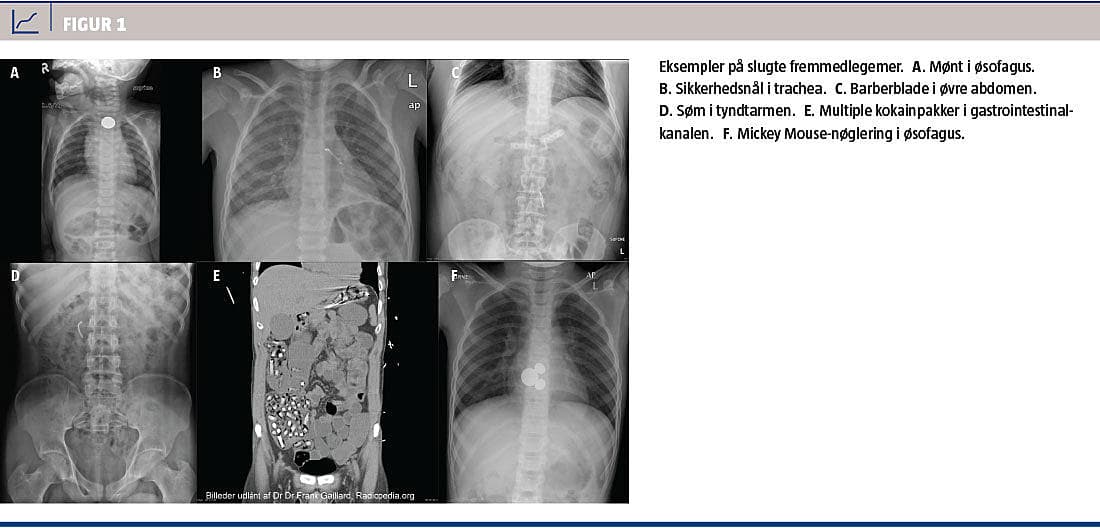

Anamnese om tidligere kirurgi og sygdom i mave-tarm-kanalen samt type, antal og tidspunkt for indtag af FL skal afklares. Ved en objektiv undersøgelse findes der normale forhold hos 90% [22]. Man foretager røntgenundersøgelse hos alle patienter som en anterior-posterior-projektion af thorax og abdomen

(Figur 1). Hos børn < 3 år skal røntgenoptagelsen dække området fra mund til analåbning [2]. Røntgenundersøgelsen kan undlades ved fastsiddende fødebolus. FL er røntgenfast hos 47-64% [4, 6]. Fiskeben, kyllingeben, træ, plast og glas kan ikke altid visualiseres på konventionel røntgen. Skiveformede FL orienterer sig i sagittalplan i trachea og frontalplan i øsofagus. Knapbatterier ses som dobbeltskiver. CT er førstevalg ved body-packers [20] og bør overvejes ved multiple FL og ved mistanke om perforation, absces eller ileus. Røntgenkontrastunder-søgelse anbefales ikke på grund af risiko for aspiration [1].